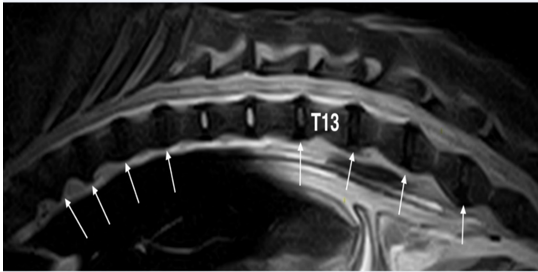

This was confirmed as generalized disc degeneration using MRI (Figure 2), at sites T3-T4, T5-T6, T7-T8, T8-T9, T13-L1, and L1-L2, without compressions or signal changes of the spinal cord (Figure 1C, 3B, 4B-C and 5). Widening of the epidural and subarachnoid space was noted (Figure 4 B-C); this alteration was considered secondary to reduced transverse diameter of the spinal cord. CSF was normal on examination. After 23 months, a new MRI was performed using a 0.3T unit (Hitachi Airis II), with turbo spin-echo T2 weighted imaging (TSET2WI= TE 120, TR 5000, and Nex 4), spin-echo T1 weighted imaging (SET1WI= TE30, TR448, Nex 2), and short tau inversion recovery (STIR= TE 25, TI 110, TR 6000, and Nex 2) in the sagittal and transverse planes, confirming the previous findings.

Figure 2: Fast spin-echo (FSE) T2 weighted image of the thoraco-lumbar spine on sagittal plane: With the exception of T10-T11 and T11-T12 discs that seem normal, all others are degenerated (white arrows).

Diagnosis: On diagnosis, widespread spondylosis and multiple disc protrusions without spinal cord compression or signal alterations were observed (Figure 5); however, the diameter was reduced, and the epidural and subarachnoid space were widened. These findings suggested concomitant DM. At that time, the owner refused the genetic test.

Figure 3: Fast spin-echo (FSE) T2 weighted images on sagittal (A) and transverse (B) planes and SE T1 weighted on transverse (C) plane, at the level of intersomatic space T12-T13: the spinal cord is significantly reduced in diameter and no signal alteration is reported in T2 weighted images (dashed arrow), while the spinal canal is replaced by epidural fat (white arrows) on a T1 weighted image on the right side of the spinal cord

Figure 4: Fast spin-echo (FSE) T2 weighted images on sagittal (A) plane, short tau inversion recovery (STIR) sequence on the transverse (B) plane and T1 weighted image on the transverse (C) plane at the intersomatic space of L1-L2: white arrows (B and C) show disc protrusion that produces only a deviation of the spinal cord, without compression. Black arrow (C) shows epidural fat that appears hyperintense, while in the STIR sequence (B) the signal is null (dashed arrow). Note that the sub-arachnoidal space appears to be enlarged (asterisk)